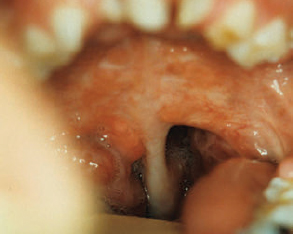

CHAPTER Patients born with cleft lip and/or palate require the care of several specialists and a number of surgical procedures and other interventions, from infancy to adulthood, to achieve total habilitation and have the opportunity to live normal and productive lives. The goals for habilitation include normalization of facial appearance and functions including improvements in soft tissues as well as skeletal, dental, and occlusal relations. Speech, hearing, and psychosocial issues are also addressed and managed. The need for multidisciplinary management using comprehensive protocols designed to address each patient’s multiple and complex needs has been well recognized, and the role of the team approach has become the gold standard of cleft care. Members are responsible for the longitudinal evaluation and coordinated care and provide for regular interactive encounters between all necessary professionals representing a variety of disciplines. They meet to communicate, collaborate, and consolidate knowledge. Extensive initial evaluation plans are made for immediate and future care based on each patient’s individual needs and the team’s treatment protocols. A prime responsibility of each team also includes careful record keeping. Collected data are studied and analyzed periodically to fully appreciate the outcome of protocols and surgical procedures, identify possible drawbacks, and modify or improve them as needed.1 Evaluation of results after cleft lip and palate repair is not easy, and several flaws are recognized in the reported outcomes of retrospective or prospective studies. Nearly 2 decades from infancy to adulthood are necessary for the completion of care and subsequent evaluation of functional and aesthetic results. Thus the final evaluation of outcomes can be problematic for several primary reasons: • Turnover of team members • Change of protocols • Introduction of new surgical procedures • Patients’ relocation • Incomplete records for services provided outside the institutions • Changes in insurance coverage • Denial of insurance coverage for some necessary services and refusal of patients to undergo final aesthetic or reconstructive procedures Many studies include a small number of patients with multifaceted problems related to the deformity, as well as significant variations in treatment protocols, timing for each procedure, surgical technique(s), and experience and skills of the individual surgeon, and many have an incomplete follow-up period.2 Furthermore, the vast majority of current studies rely primarily on subjective, not objective, evaluation. For example, evaluation of facial features using only photographs provides information about facial symmetry, but this may not be the most appropriate way to judge a surgical outcome given that only static results are displayed and asymmetries or irregularities during animation could have been missed. The need for well-planned, well-designed, ethical, multicenter, prospective long-term studies has been well recognized. Such studies could provide quantifiable, nonbiased data and assist in improving patient care by addressing remaining controversial issues, such as appropriate timing for specific surgical procedures as well as selection of the best possible surgical technique(s). Until such studies are available surgeons must rely on data from existing studies and honest evaluation and analysis of their own results to provide the best possible care for their patients. With improved knowledge and collective experience, extensive long-term follow-up studies, appropriate coordinated care, cooperation among specialists, close monitoring, and analysis of short- and long-term results, as well as adequate funding to cover all necessary services, management of patients with facial clefts could further improve so consistently superior results can be achieved. Residual deformities have several primary causes: • Failure to recognize and treat the full spectrum of problems associated with facial clefting • Tissue deficiencies inherent to the cleft • Inappropriate timing • Poorly designed and performed procedures • Complications of the initial surgery Additional operations and revisions are required to correct deformities that were not addressed during the primary procedure, inherent tissue deficiencies, maxillofacial changes, and/or scar contractures. Additional procedures might also necessary to address otologic, dental, and speech problems and to improve persisting residual functional and aesthetic deformities. These procedures have been described at length in many textbooks and scientific articles. The average number of procedures necessary to achieve the best possible functional and aesthetic habilitation has not been clearly defined, and it is difficult to accurately estimate from existing data. In some studies secondary procedures, such as alveolar bone grafts and orthognathic surgery, are barely mentioned or included, and most studies do not include dental or otologic procedures in the average total numbers. Thus the total number of procedures or interventions is definitely underreported.3 Few surgeons have reported on the actual average number of procedures required to achieve the best possible long-term results.4–7 More recently David and others8–10 presented a series of papers entitled “From Birth to Maturity: A Group of Patients Who Have Completed Their Protocol Management” that included evaluation of patients with unilateral cleft lip and palate, isolated cleft palate, and bilateral cleft lip and palate. These unique studies are based on the experience of one surgeon and a center with a relatively stable patient population. Despite the lack of detailed longitudinal data, however, there is general agreement that regardless of protocol of care, subsequent procedures will be necessary from infancy to adulthood to achieve the best possible functional and aesthetic results and complete habilitation. The objectives of primary cleft lip repair are to establish anatomy and symmetry of the upper lip and nostrils and improve form and function. Criteria for satisfactory cleft lip repair, regardless of surgical technique, are summarized in Box 40.1. The value of preoperative orthopedics and lip taping in the final outcome is still debated. Repositioning of the maxillary alveolar segments in an anatomically correct position could facilitate a tension-free closure and allow for a simultaneous periosteoplasty in selected cases. Such an approach might result in a better appearance of the lip, alveolus, and nose and potentially reduce the total number of secondary procedures. At my center we use a modified nasoalveolar molding device to improve the position of the maxillary segments and facilitate nasal repair.11 Intermediate results appear promising, but definitive final long-term results of such interventions and potential adverse effects on maxillofacial growth are only partially available.12–14 Disadvantages of this protocol include the additional expenses and the need for multiple visits for adjustment, but these could be offset by the reduction of subsequent surgical procedures. Summary Box Common Complications Related to Cleft Lip and Palate Repair Cleft Lip Cleft Palate • Dehiscence • Bleeding • Infection • Unfavorable scarring • Discrepancies of the upper lip • Intraoral (mucosal) scar contracture • Orbicularis oris deformities • Mucocutaneous deformities • Vermilion deformities • Sulcus obliteration • Combinations • Dehiscence • Palatal failures/fistulas • Scar contracture • Velopharyngeal deficiencies • Skeletal deformities • Combinations Preoperative orthopedics for bilateral clefts with repositioning of the prominent premaxilla is more widely accepted. Several techniques have been described to achieve premaxilla repositioning. We use a noninvasive appliance, fabricated by our prosthodontist, which is helpful in optimizing the position of the premaxilla and, if needed, combined with nasoalveolar molding extensions. Negative effects on facial growth and development have not been observed. Several weeks are necessary to achieve a favorable repositioning of the premaxilla and improve alignment with the maxillary segments.15 In extreme cases, and when conservative management is unsuccessful, premaxillary setback can also be used to bring the premaxilla within the occlusal plane and facilitate a tension-free lip and palate repair.16 Immediate surgical complications after cleft lip repair are extremely rare but include bleeding, infection, and dehiscence. Early wound dehiscence is rare and primarily is a result of technical errors or closure under tension or occurs after accidental trauma. In such cases, immediate management with minimal débridement, additional undermining as needed, and layered closure without undue tension is recommended (Fig. 40.1). • Detailed markings of all landmarks, taking into consideration the anatomy of the upper lip, alveolus, and nostrils • Accurate measurements and markings of all proposed incisions • Gentle tissue handling • Development of flaps on either side of the cleft with adequate tissue mobilization • Release of superficial and deep fibers of the orbicularis oris from their abnormal attachments • Dissection and reposition of the cleft-side lower alar cartilage in a more symmetrical three-dimensional position • Reconstruction of the nasal floor • Accurate skin, muscle, and mucous membrane union • Closure under minimal or no tension to achieve the optimal scar • Symmetrical vermilion border with alignment of the vermilion (dry lip) and the mucosa (moist lip) • Slight eversion of the lip, accurate reconstruction of the Cupid’s bow and the tubercle, and correct alignment of the white roll • Symmetrical nostril floors and elongation of the columella, as needed Fig. 40.1 (a) A 7-month-old patient 7 days after bilateral cleft lip repair with complete dehiscence on the left side after a fall at home. (b) After cleansing and minimal débridement. (c) The lip was repaired again in layers. (d) Two months later the lip has healed well. Residual lip deformities might vary from minor ones corrected with minimal interventions, to major asymmetries and deformities that may even require complete revision of the lip repair. It is beyond the scope of this chapter to describe all residual deformities and present all reported techniques and modifications. The most common deformities are presented with the recommended treatment and with reliable techniques based on my experience and time-honored procedures. A revision lip surgery should only be chosen after extensive consultation with the family and the child and with a clear understanding of the expectations. Objectives of the procedures, the surgical plan, and possible outcomes should be outlined and false expectations dispelled. Timing can affect the outcome and should be taken into consideration, but decisions should be individualized and not made in a rigid and dogmatic fashion. Procedures should be postponed if an adolescent is not willing to have surgery, even when parents desire and request it. Conversely, some procedures might be scheduled earlier than initially planned if there is evidence of a negative psychologic effect on the child. If possible, several procedures should be bundled to reduce time away from school or work, additional psychological trauma from multiple interventions, and cost. Before planning a revision, the entire lip, including the oral mucosa; sulcus; alveolus; and nostrils should be examined at rest and during animation. The deformity should be analyzed and all contributing factors taken into consideration. All necessary soft tissue landmarks should be appropriately marked and measured. All contributing elements to the deformity should be corrected in one setting whenever possible (Fig. 40.2). Careful planning, appropriate timing, and detailed execution are extremely important, because failure of the revision procedure to correct the deformity may result in additional scarring and tissue loss that could further reduce the chances for adequate habilitation.3,17 Wide, poorly healed persistent scars of the upper lip with unsightly stitch marks are encountered less commonly. They result from closure under tension and the use of tight sutures left in place for too long. Such problems can be avoided in most cases by using fine techniques with meticulous tissue handling and a tension-free closure, fine sutures, or even tissue adhesives. Other aggravating factors include postoperative bleeding, infection around the suture line, and dehiscence. The surgeon should be able to differentiate these unsightly scars from the hypertrophic scars that form without apparent cause and usually fade away slowly without need for additional surgical intervention. Timing for scar revision is important to the final outcome. Waiting several months before a revision to allow the scar to mature is recommended. After careful evaluation, the appropriate surgical procedure should be planned. Elliptical excision of the scar, with precise approximation and closure after limited undermining, is the simplest solution. This technique, however, can only be applied for relatively narrow scars. Excision of wider scars might result in defects that, if directly repaired, might cause distortion of the lip in the vertical or horizontal axis and/or narrowing of the nostril sill. To prevent these problems, the excision should be planed accordingly, preferably with a wavy style of excision, undermining on either side of the defect and performing tissue rearrangement as needed. Geometric tissue rearrangement with z-plasties and other techniques should be avoided, because the subsequent scar will permanently carry the marks of such designs. Dermabrasion is helpful in some cases and is primarily recommended for improvement of residual surface irregularities. Finally, single hair micrografts have been recommended for male patients to further camouflage the lip scar and allow for a moustache.18 An excessively long lip on the cleft side is truly technique related. It has been encountered with LeMesurier and the initial Tennison repairs but can result with other techniques as well. Correction is difficult, because in most instances all lip layers are involved. If the discrepancy is minor, it can be corrected with appropriate excision just below the nostril sill. If a significant discrepancy is present, however, the lip should be completely divided after appropriate markings are made and carefully repaired in layers. Fig. 40.2 The entire lip, including the oral mucosa; sulcus; alveolus; and nostrils should be evaluated and all necessary soft tissue landmarks marked and measured. A short lip results primarily from straight-line closures, inadequate rotation, and advancement techniques and scar contractures. Small discrepancies can be corrected with elliptical, diamond-shaped, or wavy excisions of the entire scar and closure after adequate undermining. If needed, a z-plasty can be designed and incorporated with the revision, preferably below the nostril sill. The drawback to such approaches is the small gain achieved and the addition of a Z-shaped scar on the lip. If a significant discrepancy exists, the only solution is to redo the lip repair, extending the rotation advancement design to increase lip height (Figs. 40.3 and 40.4). Fig. 40.3 (a,b) This 5-year-old had a significant residual deformity of the lip and nose including a short lip, dehisced orbicularis oris, and lateral flaring of the cleft-side nostril. Excess skin of approximately 1-cm width in the horizontal axis was identified during markings. (c) Excess skin with corresponding vermilion was excised, the orbicularis oris was approximated after undermining, and the nostril floor was repositioned after reduction of the skin of the sill. (d) Immediate postoperative result. Fig. 40.4 (a–c) This patient had a significant residual deformity after bilateral cleft lip repair. He had a short lip, no orbicularis contact in the midline, exposed moist mucosa in the vermilion, and bilateral scar contractures in the oral mucosa. (d) Appropriate tailoring of the philtrum, approximation of orbicularis oris muscle fibers in the midline, excision of redundant vermilion, release of intraoral scars, and coverage of the mucosal defect with sliding flaps. (e) Final result 4 months after revision with improved symmetry and balance. The tight upper lip deformity primarily occurs in patients with bilateral clefts. Local tissue rearrangement and even revision of the repair is not beneficial in most cases because of the limited tissue availability and scarring. Because of the paucity of tissue, a flap from the lower lip, an Abbé flap, should be added after all scarred tissue is removed.19 This procedure is not recommended for young children because of the temporary junction of the lips. To achieve a superior functional and aesthetic result and a balanced profile, accurate design of the dimensions of the flap to match the created defect, placement of the flap in the center of the lip to simulate the philtrum, and placement of the final scars to simulate the philtrum columns are necessary. The width of the flap should be adequately planned and narrower from the normal philtrum to encounter for subsequent widening from natural tension. The layers of the flap should be sutured carefully to the corresponding layers of the lateral lip segments and the upper buccal sulcus20 (Fig. 40.5). Fig. 40.5 (a) This woman had a very short and tight upper lip after bilateral cleft lip repair and a subsequent revision. The upper sulcus was completely obliterated. (b) Design of the Abbé flap. (c) Design of the flap and proposed areas of inset on the upper lip. (d) At 3 weeks postoperatively, before division and inset of the flap. (e,f) Final result 15 years after division and inset of the flap demonstrating improved symmetry and balance of the upper lip. (b Reproduced from Bentz ML, Bauer BS, Zuker RM. Principles and Practice of Pediatric Plastic Surgery. 2nd ed. New York: Thieme Publishing; 2016.) Reconstruction of the orbicularis oris muscle is incorporated during lip repairs. Failure to release and fully reconstruct the muscular sling or partial or complete dehiscence of the muscle repair will result in unsightly bulging of the muscle on either side of the lip scar or depressions and asymmetries that are further accentuated during anima tion, giving the lip an unnatural look. For small deformities, the lip scar can be excised and the muscle fibers identified and freed from their abnormal attachments and sutured together. When a significant deformity or dehiscence exists, a total lip repair should be planned with all anatomic elements of the lip dissected and repaired correctly (Figs. 40.6 and 40.7). Fig. 40.6 (a,b) Complete dehiscence of orbicularis oris excess skin, including partially obliterated upper buccal sulcus and excess tissue in the horizontal axis. (c) Excision of excess scar, excess skin, and vermilion according to markings. (d) Layered closure. Fig. 40.7 (a) Residual lip and nose deformity after unilateral cleft lip repair. The patient had a short lip, dehiscence of the lower third of the orbicularis oris repair, lateral fullness of the vermilion depression, scarring of the nostril sill, and lateral deflection of the lower alar cartilage with nostril asymmetry. (b) The orbicularis oris fibers were identified after undermining and reapproximated. (c) The nasal deformity was simultaneously corrected through an open rhinoplasty approach. Mucocutaneous deformities result from poor alignment of the white roll during the initial lip repair. Accurate placement of the skin suture on the white roll assists in preventing this problem. This deformity is primarily corrected with an elliptical or rhomboid excision of the scar and accurate reapproximation of the mucocutaneous junction. Only a few millimeters in vertical height can be gained with this technique. As an alternative, a small z-plasty can be used to allow for interposition of the vermilion and a skin flap and ultimately results in realignment of the mucocutaneous line. Lack of bulk or poor alignment of the vermilion can cause several deformities. Lack of bulk is primarily a result of inherent tissue deficiency, dehiscence, or failure to approximate the lower portion of the orbicularis oris muscle during the initial lip repair. To correct such deformities, the scar at the vermilion border should be excised; the fibers of the orbicularis are identified after limited undermining and approximated carefully with eversion of the margins. In the past, small local filler grafts or autologous fascial grafts were recommended. Currently, autologous fat grafting is considered to be the procedure of choice and has been added to my armamentarium.21 Minimal whistling deformities of the lip resulting primarily from scar contractures in the area of the vermilion and the mucosa of the lip can be corrected with z-plasties by placing the central limb on the existing scar. A central whistling deformity with good height of the lip occurs primarily after repair of bilateral clefts of the lip. For this residual deformity, lipofilling is also considered as long as an adequate sulcus is present and there is no mucosal contracture. Vermilion fullness on the cleft side of the lip can also be encountered. As long as the rest of the lip is not involved, this deformity can be corrected with a horizontal elliptical excision. The surgeon should be very careful to avoid overresection or mismatch between the dry and moist portions of the lip. Fig. 40.8 (a,b) After two revisions, this patient had residual deficiency of the vermilion border and bulge of the orbicularis oris muscle lateral to the lip scar. (c) Intraoral scarring and contracture accentuating the deformity. (d) Preoperative marking on the skin and vermilion. (e) Release of the intraoral scar with direct approximation of the mucosal flaps (arrows) after undermining. (f,g) Final result 2 years after reconstruction; the upper lip is well healed and soft. The upper lip might also appear short because of mucosal scar contracture or even obliteration of the sulcus (Fig. 40.8). This contracture should be released independently or managed along with other deformities of the lip. In most cases of unilateral cleft lip, release can be achieved with excision of the scar, and reconstruction of the mucosal defect and mucosal rearrangement can achieve full coverage; raw surfaces will result in further scarring, contracture, and deformity. Despite advanced techniques for bilateral cases, some patients still present with partial or complete obliteration of the upper labial sulcus.22 In such cases, the lip will appear short and retracted, with incisor and even gingival show. Complete release of the soft tissues from the premaxilla and coverage of the subsequent defect are necessary. Skin or mucosal grafts were used in the past to resurface the sulcus and complete the vestibuloplasty. The surgeon should avoid denuding the premaxilla from its periosteum, completely release the lip, suture the graft in place with absorbable sutures, and stabilize it with a small stent. I currently almost exclusively use mucosal flaps advanced from the lateral lip segments with superior results and reserve the use of grafts only for the rare occasion that the defect cannot be covered with flaps because of significant preexisting scarring of the labial mucosa (Fig. 40.9). The primary objective of cleft palate repair is to establish the anatomy of the hard and soft palate as close to normal as possible, provide an adequate mechanism for velopharyngeal function and speech, and improve middle ear function. Regardless of surgical technique, the final goal should be a palate of adequate length, with reconstruction of the muscular velopharyngeal sling, and approximation without tension. Timing for cleft palate repair has been controversial because of the potential negative effects on facial growth. Since the landmark publication by Dorf and Curtin,23 most surgeons agree that early palatoplasty, before the child’s first birthday, has beneficial effects on speech without detrimental effects on facial growth. We follow this protocol with the understanding that timing of palatal repair should not be determined by age only but should be individualized, taking into consideration anatomic findings and the patient’s health. With careful palatal dissection, complete muscle dissection and approximation, flap approximation without tension, and avoidance of large residual lateral raw areas, speech results have been superior and skeletal deformities reduced. Further longitudinal studies are necessary to fully clarify conflicting issues, but based on the existing information, it seems reasonable to recommend early palate repair for most patients to improve speech outcome. The potential negative effect on maxillofacial growth should not be overlooked; it must be taken into consideration and closely monitored.24,25 Fig. 40.9 (a) Near-total obliteration of the upper buccal sulcus in a patient after bilateral cleft lip repair. (b) After excision of the scar and exposure of the maxilla a significant mucosal defect remained. (c) Immediate postoperative result after coverage of the defect with sliding mucosal flaps. (d) Final result several months after the reconstruction; the patient has a well-maintained upper sulcus. Despite advances in techniques and better understanding of their effects on speech and facial growth, several complications or failures requiring additional surgery are still encountered. The most significant ones include the following: • Palatal repair failures and fistulas • Velopharyngeal deficiencies • Skeletal deformities (see Chapter 43) There is a wide range of reported incidence of palatal fistulas after palatoplasty, and various classifications are used. For the purposes of this discussion only fistulas presenting in areas of previous palatal repair are included. Incidence seems to be independent of the surgical technique but is significantly higher in bilateral cases. Palatal fistulas represent failures of the surgical technique and might be due to several factors from poor designs to technical errors. Such errors might include incomplete dissection or mobilization of the flaps, failure to completely detach the muscles of the soft palate from their abnormal attachment to the hard palate, incomplete approximation and suturing of all soft tissue layers, closure under undue tension, postoperative bleeding between the oral and nasal layers, or infections. Anterior fistulas just behind the premaxilla may occur in patients with wide bilateral clefts in whom, because of a paucity of soft tissues in the area, complete closure was not possible or closure under tension resulted in dehiscence.10 Fistulas may become evident immediately after the palatoplasty or may develop several years later during orthodontic treatment and transpalatal expansion. Early dehiscence, particularly in the posterior third of the soft palate, is caused primarily by errors in technique or accidental trauma. If dehiscence is identified early, it should be repaired immediately to allow for early habilitation, prevention of contracture, and subsequent shortening of the soft palate. Larger fistulas may become symptomatic, resulting in nasal regurgitation of saliva, fluids, and food particles and affecting speech, causing hypernasality and articulation disturbances. Some surgeons propose conservative management for asymp tomatic fistulas, whereas others recommend closure of even small fistulas given that regurgitation of food and liquids into the nasal cavity might result in constant irritation of the nasal mucosa. This may cause swelling, occasional bleeding, and have potential effects on breathing, speech, or oronasal hygiene. I recommend waiting for several months after the palatoplasty before closing a palatal fistula, because in the early postoperative period the tissues around the fistula are inflamed, edematous, and friable. Thus attempts for repair are more likely to fail. Reported success rates vary widely.26 Better understanding of the timing and mechanics of fistula repair increases the rate of success and significantly reduces the possibility of recurrence. Large fistulas should be closed as soon as possible, but the temporary option of an obturator should also be kept in mind (Fig. 40.10). Premaxillary setback can be used when the premaxilla cannot be retropositioned to the occlusal plane (Video 40.1). This should be done after appropriate palatal expansion and even combined with anterior fistula closure and alveolar bone grafts (Fig. 40.11). Fig. 40.10 (a) This 5-year-old had a large anterior palatal fistula with food and air escape to the nasal cavity after palatoplasty and three failed revisions. (b) An obturator was fabricated by a prosthodontist to provide temporary functional and aesthetic resolution of the problem and immediate improvement in speech. (c,d) The obturator in place. Before planning a fistula repair, the surgeon must fully appreciate the anatomy: the length of the palate, size and location of the defect, and tissue availability. The surgeon should also evaluate the movement of the soft palate and the possible inadequate dissection and release of the muscles of the soft palate during the initial surgery.3 Complete speech evaluation and even endoscopy might be necessary to obtain all preoperative information and plan management accordingly. Each area of the palate has different requirements with respect to fistula closure. The surgeon should first decide whether the surrounding tissues are adequate for the closure or whether additional tissues, brought primarily from other areas of the oral cavity, will be necessary. For small dehiscences or fistulas in the area of the uvula or soft palate with adequate palatal length and movement and with no evidence of velopharyngeal deficiency, the dehiscence or fistula should be repaired with a relatively straightforward procedure without extensive dissection. The margins of the dehiscence or fistula should be excised and the palatal scar extended anteriorly and posteriorly of the fistula, as needed, to allow for better visualization and mobilization of the nasal lining and muscles and a tension-free, layered closure (Fig. 40.12). Fig. 40.11 (a–c) This 8-year-old had significant protrusion of the premaxilla, collapse of the lateral maxillary segments, and a bilateral oronasal and anterior palatal fistula after bilateral cleft lip and palate repair. (d) Near completion of palatal expansion. (e) After completion of orthodontic expansion setback of the premaxilla allowed for simultaneous closure of palatal and oronasal fistulas and bone grafting of the maxilla. (f) Final appearance with improved facial symmetry and harmony. Fig. 40.12 (a) Dehisced uvula and posterior third of the soft palate with a dehisced muscular sling. (b) Extension of the incision to the hard palate with undermining over and under the muscles and release of the muscles from their abnormal attachment. (c) Final result after layered closure. For larger fistulas extending to the junction between the hard and soft palate, attempting to directly repair the fistula might result in undue tension with subsequent failure. Lateral relaxing incisions with undermining and mobilization of the mucoperiosteum of the hard palate will facilitate a tension-free layered closure in most cases. The muscles of the soft palate should be released from their abnormal attachment on the posterior wall of the hard palate. Failure to do so will prevent adequate muscle approximation and provide no improvement of the palate movement during speech (Fig. 40.13). A critical issue with repair of such fistulas is the adequacy of nasal lining, because failure to repair the nasal surface of the palate might predispose to contracture or recurrence. For relatively small defects a z-plasty of nasal lining flaps is adequate, whereas for larger defects the introduction of fresh tissue, such as buccal flaps, might be necessary.3 A superiorly based pharyngeal flap can be used when the palate is relatively short and velopharyngeal insufficiency (VPI) is also present. The surgeon should first consider redoing the palatal repair and retropositioning the palate at the time of fistula repair or using a pharyngeal flap to provide additional support, in conjunction with correction of the VPI (Fig. 40.14). Fistulas of the hard palate represent a different challenge. Some surgeons have suggested the use of local turnover flaps from the periphery of the fistula for nasal lining closure and the use of local rotation or transposition flaps of palatal mucoperiosteum for oral coverage. These flaps occasionally can be successful. For larger defects, I prefer to redo the palatoplasty with complete mobilization of bilateral palatal flaps; repair of the nasal lining directly or with vomer flaps, if needed; and reapproximation of the palatal flaps without tension (Fig. 40.15). When vomer flaps are not available, a patch of acellular dermal matrix can be used to completely repair the nasal defect before suturing the palatal flaps.27 I place a couple of through-and-through sutures from the palatal flaps to the acellular dermal matrix to obliterate the dead space between the two layers and provide direct contact of the matrix with the well-vascularized palatal flaps. For large palatal defects resulting from multiple interventions and failures, the options for successful reconstruction are virtually absent. In such cases, paucity of local tissues can be addressed with the addition of tissue recruited from the oral region in the form of pedicle flaps. Free vascularized flaps have also been suggested to manage extremely large defects. The surgeon should be careful when dealing with such complex conditions, individualizing the plan and designing each reconstructive procedure with extreme care, because additional failure could result in further tissue loss and magnify the defect. The surgeon must also know when to stop and remember that some patients could be better served with an obturator, which of course is not the first choice for management of fistulas but is a viable option when managing multiple failures. Fig. 40.13 (a) Residual palatal fistula in the junction between the soft and hard palate many years after palatoplasty. (b,c) Margins of the fistula were stripped from the mucosa; all layers of the soft palate including oral mucosa, muscles, and nasal lining were identified; palatal flaps were mobilized after extensive undermining to achieve a tension-free closure; and the defect was repaired in layers. (d) Final result 14 months after repair. Fig. 40.14 (a,b) Small palatal fistula with complete dehiscence of the palatal muscles and uvula and significant hypernasality. (c,d) The margins of the fistula were excised, the scar of soft palate was incised to the junction with the hard palate, palatal muscles were detached from their abnormal attachment in the hard palate, and a superiorly based pharyngeal flap was raised (arrow) and sutured to the palate. (e) The palate was then closed in layers. Fig. 40.15 (a) A large anterior palatal fistula in an 8-year-old after cleft lip and palate repair. (b,c) The margins of the fistula were incised and flaps were turned over to achieve complete closure of the nasal lining. Bilateral flaps were elevated and approximated without tension. (d) Palatal flaps were elevated to fully visualize and delineate the nasal margins of the fistula before repair. (e) Final result several months after the reconstruction, demonstrating an intact palate without fistula recurrence. Large anterior palatal fistulas not treated previously and those caused by failures of previous attempts and presenting with stiffness or lack of elasticity of the palatal tissues might require additional well-vascularized tissue for a successful closure. Tongue flaps can be very helpful in the management of such difficult cases (Fig. 40.16). Two stages are required with this technique. Eating or speaking is not restricted during the interim period. Planning and attention to all technical details are important. The extent of the fistula should be delineated completely. Turnover flaps from the margins of the fistula should be used, if feasible, to achieve full closure of the floor of the nose. The palatal tissues around the fistula should be undermined circumferentially for a few millimeters to allow for adequate insetting and suturing of the tongue flap around the defect. I prefer anteriorly based flaps designed a little wider than the size of the defect and 5 to 6 cm long to prevent tethering of the tongue during speech or eating. The flap should be about 0.5 cm thick and consist of mucosa and muscle fibers. The donor site is closed primarily, almost to the base of the flap. The flap is then inset around the margins of the fistula using absorbable mattress sutures. After 2 to 3 weeks, the pedicle is divided and inset in the posterior area of the fistula after freshening of the palatal margins. The remaining pedicle is discarded, and additional sutures are placed to completely repair the tongue defect. There have been no problems with tongue mobility or swallowing after this procedure, although there are isolated reports of negative effects on speech and articulation.28 They occur with bulky flaps, which interfere with the position of the tongue during speech and could have been prevented with careful planning, designing, and insetting of the flap. Fig. 40.16 (a) A large anterior palatal fistula after multiple interventions in an 8-year-old. (b,c) Turnover flaps from the margins of the fistula were first used to completely repair the nasal lining. (d,e) An anteriorly based tongue flap measuring 5 by 2 cm was used. (f) Tongue flap inset around the margins of the fistula. (g,h) Final result with complete healing of the fistula and excellent tongue movement. Fig. 40.17 (a) Oronasal and large anterior palatal fistulas simultaneously covered with a large labial mucosa flap at the time of bone grafting of the residual alveolar cleft. (b,c) The bone graft and palatal fistula were simultaneously covered with the labial flap. The donor site was closed primarily. Another popular technique is the use of bucket-handle flaps from the upper labial sulcus to manage large anterior defects. These flaps are random but dependable. Attention to the design and technical details is again very important. Preexisting scars from the lip repair should be taken into consideration; obliteration of the buccal sulcus should be avoided (Fig. 40.17). A paucity of tissue in the area of the junction between the hard and soft palate, in both the oral and nasal surfaces, can be managed with buccal mucosa flaps. These flaps are designed on the buccal mucosa, approximately 2 cm wide and of appropriate length to reach the defect. The base of the flap should be placed anterior to the maxillary crest and tunneled under the palatal tissues, turned so the mucosa faces the nasal cavity and sutured to the defect of the nasal lining. Alternatively, the flap can be used to replace missing oral tissue. In such cases, the palatal tissue must be incised to allow for inset of the flap.29 The buccinator and facial artery myomucosal flaps could be viable alternatives for larger defects.30,31 These flaps are dependable and have a long pedicle based on the facial and buccinator pedicles but are bulkier and sometimes difficult to deliver to palatal defects. Despite better understanding of the physiology of speech, the effects of early palate repair on speech outcome, and the improvement of surgical techniques, an average of 20% of patients will have residual velopharyngeal disturbances after cleft palate repair. This rate does not seem to be influenced significantly by the surgical technique used for the palatoplasty.32–34 Close cooperation between the surgeon and the speech pathologist is necessary to obtain appropriate data, fully appreciate the condition, and prescribe the most appropriate individualized plan. Accurate diagnosis is cardinal for a successful outcome. Before testing, a detailed history should be obtained to gain information on previous orofacial and nasal procedures, feeding or swallowing problems, nasal regurgitation, speech problems, and frequent ear infections. When surgical management of the velopharyngeal valve is anticipated, we include questions to determine whether nasal airway obstruction exists. These responses, and the results of other diagnostic tests, determine whether the nasal airway needs to be managed to increase patency before an additional resistive load, such as a pharyngeal flap, is introduced into the airway.35 Techniques and measurements used to assess velopharyngeal function generally can be classified into three categories and are summarized in Table 40.1. If after completion of a course of speech therapy and extensive evaluation a determination of a need for additional treatment is made, the following options can be considered: • Revision palatoplasty • Furlow double Z-opposing plasty • Superiorly based pharyngeal flap • Sphincter pharyngoplasty • Retropharyngeal implants or fat grafting • Prosthetic management (for nonsurgical candidates) Revision palatoplasty is recommended when the muscles of the soft palate were not properly released and the muscular sling was not properly constructed during the initial procedure.36 A double Z-opposing plasty can also be used and can provide superior speech results, because of the palatal lengthening.37,38 For relatively small gaps, fat injections in the posterior aspect of the soft palate and the pharyngeal wall are gaining some popularity.39 For most other cases, a superiorly based pharyngeal flap or a pharyngoplasty are considered to be procedures of choice.40–42 Some surgeons still recommend augmentation of the posterior pharyngeal wall with various autogenous or alloplastic materials; prosthetic rehabilitation is reserved for surgical failures or for patients with significant medical problems who are not considered good candidates for a surgical procedure.43,44 Table 40.1 Techniques and measurements of velopharyngeal function